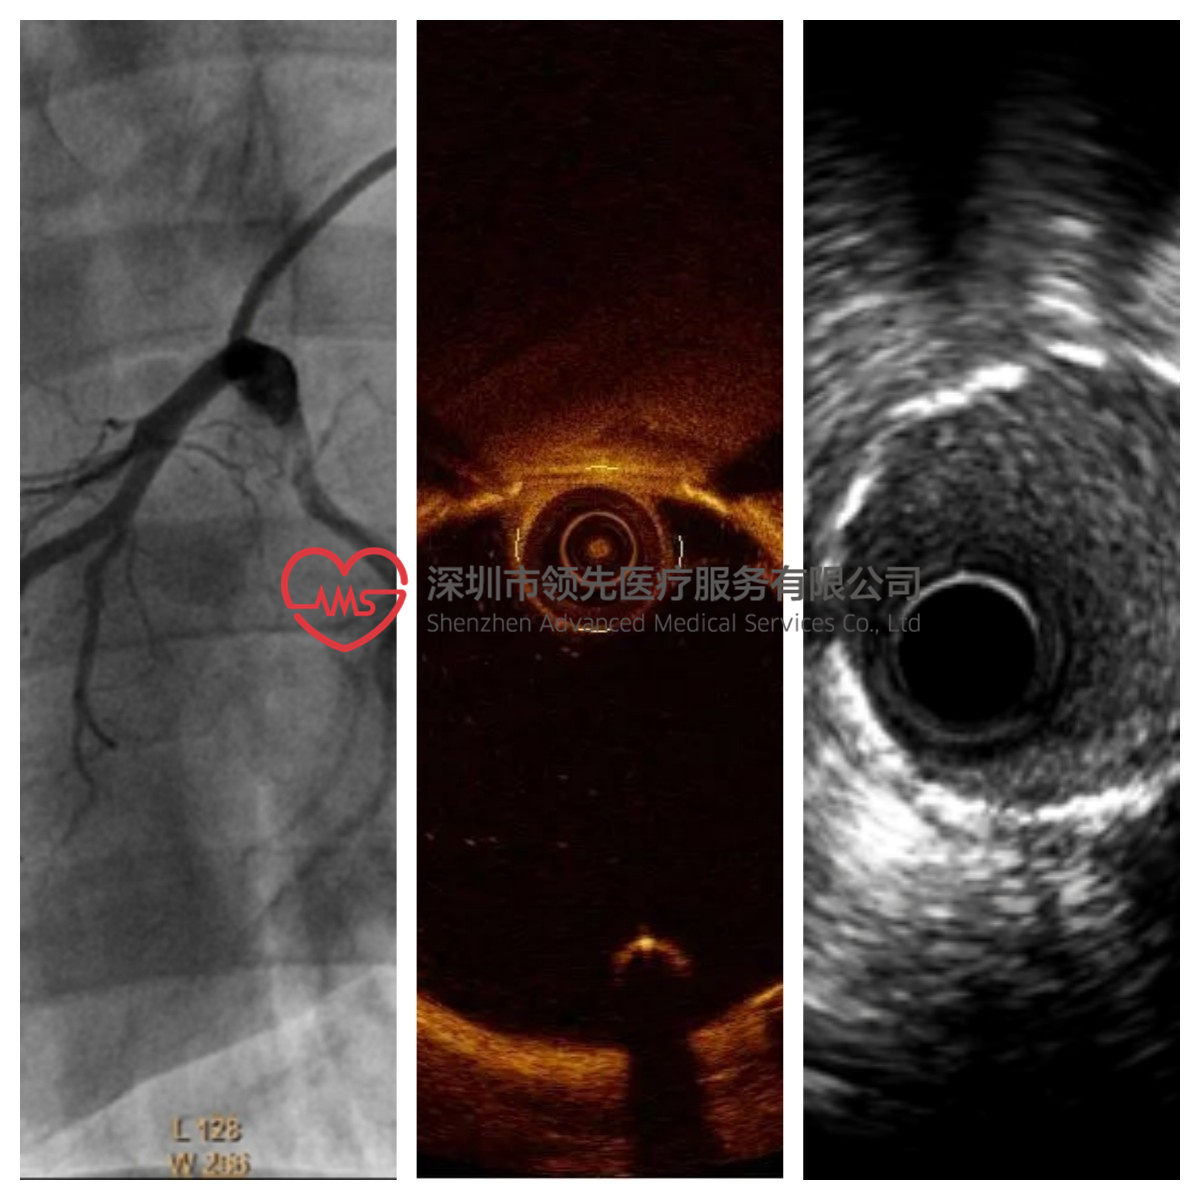

心脏冠脉支架植入需要特定导管室,以及影像设备,试验开始时从股动脉穿刺,插入穿刺鞘和导丝,经鞘管沿导丝将导管送至冠状动脉开口位置,造影观察冠状动脉情况,沿导丝送入球囊支架系统扩开支架,经OCT探查管腔情况,完成植入。

植入过程如图3所示,植入后造影图如图4所示。

图4 植入影像学检查▲